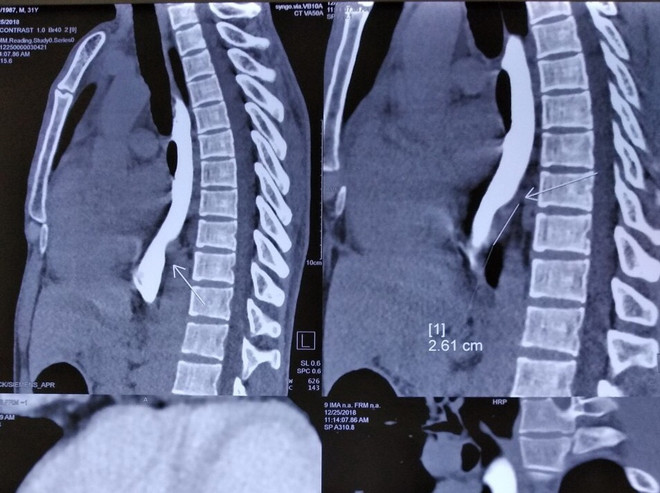

Bệnh viện K: Nội soi 3D lồng ngực mở u xơ lấy dị vật xương cá ảnh 1Phim chụp X quang của bệnh nhân. (Ảnh: PV/Vietnam+)

Sau khi chụp chiếu, làm các chỉ định, xét nghiệm cần thiết và nội soi dạ dày, thực quản anh H. được chẩn đoán có khối u xơ dưới niêm mạc thực quản.

Các bác sỹ đã lấy trọn vẹn tổn thương viêm xơ ở thực quản kích thước 3x4cm trong đó có dị vật xương cá.